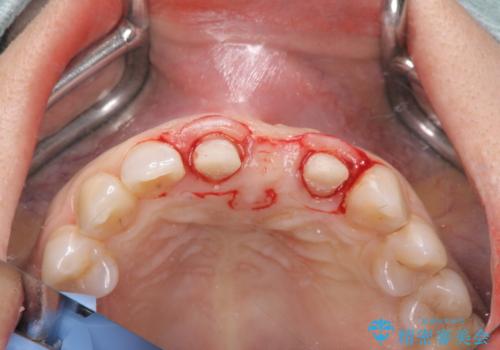

根管治療を行ったのち、歯周外科を行うことで、欠損部の歯ぐきの厚みを出し、縁上歯質を獲得することで、長期的な予後の見込めるブリッジを製作できる環境を整備していきます。

歯周外科をおこなったことで歯ぐきのラインを整え、脱離しないような前歯のブリッジを作製することができました。